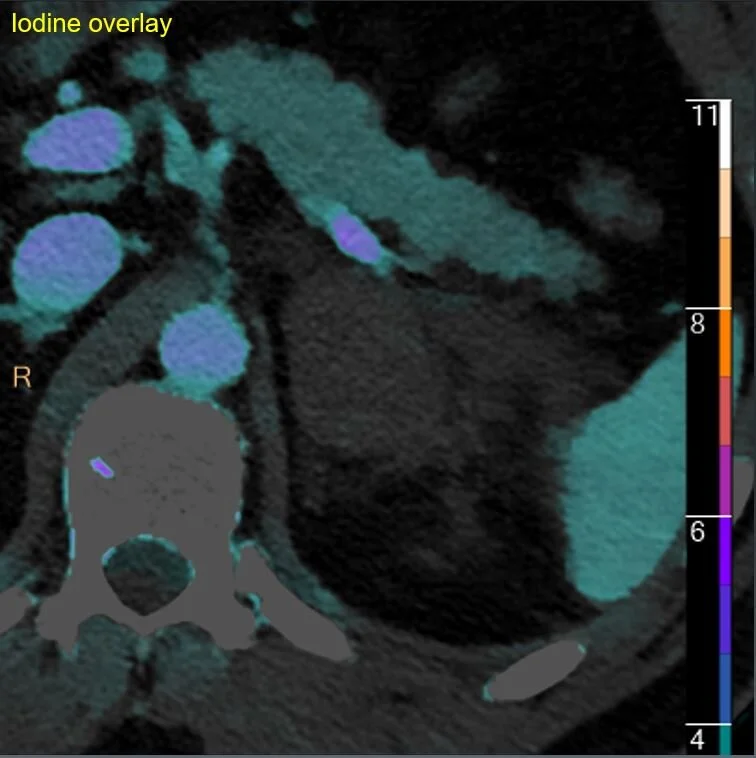

Spectral CT images show the “mass” is hyperdense on virtual non-contrast and has no iodine uptake. This is just a typical adrenal hematoma. On closer inspection, patient had a couple of rib fractures, but no other evidence of trauma.

Iodine map: Absolutely NO uptake!

Iodine overlay confirms.